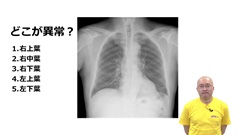

■Dr.長尾のナースのための胸部X線クイズ

看護師に必要なのは診断ではなく、異常に気付く力。異常影の手がかりとなるのは、シルエットサインです。

症例写真を提示した実践的なクイズ形式で、胸部X線検査画像のシルエットサインと異常影を見つける技を長尾先生がわかりやすく伝授します。解説時には、肺の模型やCT画像も提示。肺の立体構造を可視化して説明するため、胸部X線写真から肺のどの部位が悪いのかを見抜く力が磨けます。

腕試しに挑戦するとともに、「X線写真からここまでわかるの!?」という感動をぜひ体験してください。